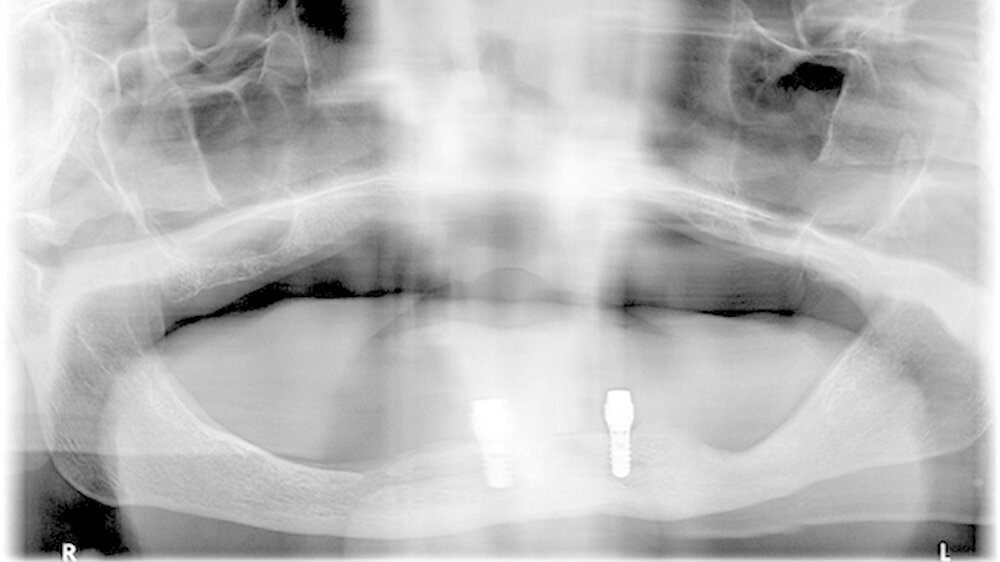

Die Patientenkohorte umfasste acht Männer und elf Frauen mit einem mittleren Alter von 85,7 ± 6,6 Jahre. Die 19 Patienten erhielten je zwei Implantate mit acht Millimeter Länge. Der Ernährungszustand (BMI und Blutmarker) und kognitive Zustand (MMSE) wurden analysiert. Zudem wurden die periimplantäre Sondierungstiefe und der Plaque-Index Score erhoben.

Im Ergebnis zeigte sich, dass die Implantatüberlebensrate nach fünf Jahren 94,7 Prozent betrug. Es gabein frühes und ein spätes Implantatversagen. Der Verlust von periimplantärer Knochenhöhe betrug im Mittel 0,17 mm pro Jahr. Periimplantäre Sondierungstiefe und Plaque-Index-Werte waren niedrig und stabil in den ersten zwei Jahren und danach kontinuierlich erhöht. Die Korrelationsanalyse zeigte, dass eine verminderte kognitive Funktion und Ernährungszustand kein besonderer Risikofaktor für einen beschleunigten periimplantären Knochenverlust sind.

Titel des Posters: Short Dental Implants Retaining 2-Implant Mandibular IODs In Very Old, Dependent Patients: Radiological and Clinical Observation up to 5 Years